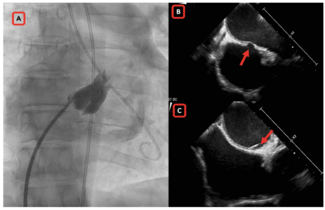

A 78-year-old man with symptomatic bicuspid severe aortic stenosis with LVEF 50% was planned for transcatheter aortic valve replacement (TAVR). His CT scan revealed calcified bicuspid aortic valve (Sievers Type 1), calcified raphe with...